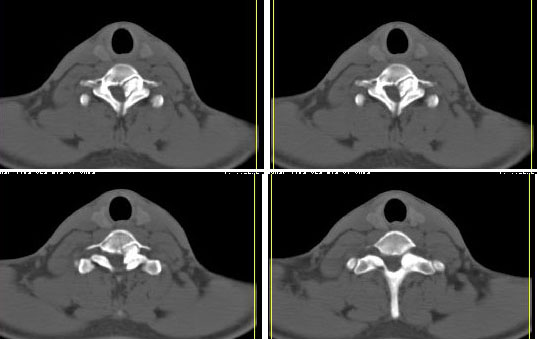

ct

椎管狭窄,其内有正常骨髓组织:考虑骨尤

或者异常骨块

标题: 考虑骨软骨瘤可能性大

椎管内骨性肿块,与第7颈椎左下关节突关系密切,向椎管内生长,第7颈椎椎体左后缘受压变形,边缘可见硬化边,与肿块间间隙清晰。mri扫描肿块内可见骨髓信号,考虑骨软骨瘤可能性大。